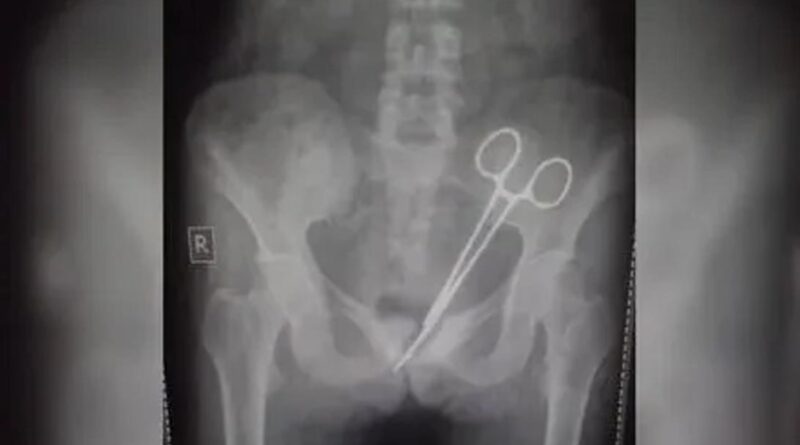

డాక్టర్ల నిర్లక్ష్యంతో 12 ఏళ్లుగా మహిళ కడుపులో కత్తెర

సిక్కింకు చెందిన బాధిత మహిళ 12 ఏళ్ల క్రితం గ్యాంగ్ టక్ లోని ఓ ఆసుపత్రిలో అపెండిక్స్ ఆపరేషన్ చేయించుకుంది. ఆ తర్వాతి నుంచి ఆమె తరచుగా కడుపునొప్పితో బాధపడింది. చాలామంది వైద్యులను సంప్రదించినప్పటికీ నొప్పి ఏ మాత్రం తగ్గలేదు. నొప్పికి కారణం కూడా వారు గుర్తించలేకపోయారు. ఈ నెల 8న ఆమె తనకు గతంలో అపెండిక్స్ ఆపరేషన్ చేసిన ఆసుపత్రికి వెళ్లి వైద్యులను సంప్రదించగా, వారు అనుమానంతో ఎక్స్ రే తీయించారు. దీంతో అసలు విషయం బయటపడింది. ఆమె పొత్తికడుపులో సర్జికల్ కత్తెర చూసి డాక్టర్లు షాక్ అయ్యారు. వెంటనే ఆమెకు ఆపరేషన్ చేసి వాటిని తొలగించారు. ఆమె ప్రస్తుతం కోలుకుంటోందని వైద్యులు తెలిపారు.